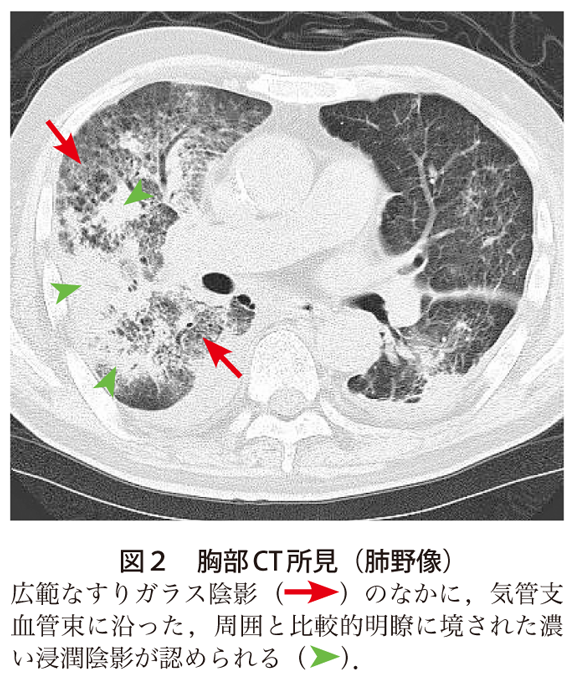

解答 解説 呼吸困難と発熱を主訴とした70歳代男性 実践 画像診断q A 羊土社 レジデントノート 実践 画像診断q A 羊土社 レジデントノート 羊土社

解答 解説 発熱と呼吸困難を主訴とした50歳代男性 実践 画像診断q A 羊土社 レジデントノート 羊土社

解答 解説 高熱 呼吸困難 意識障害で受診した60歳代男性 実践 画像診断q A 羊土社 レジデントノート 実践 画像診断q A 羊土社 レジデントノート 羊土社

解答 解説 高熱を主訴とした60歳代男性 実践 画像診断q A 羊土社 レジデントノート 実践 画像診断q A 羊土社 レジデントノート 羊土社